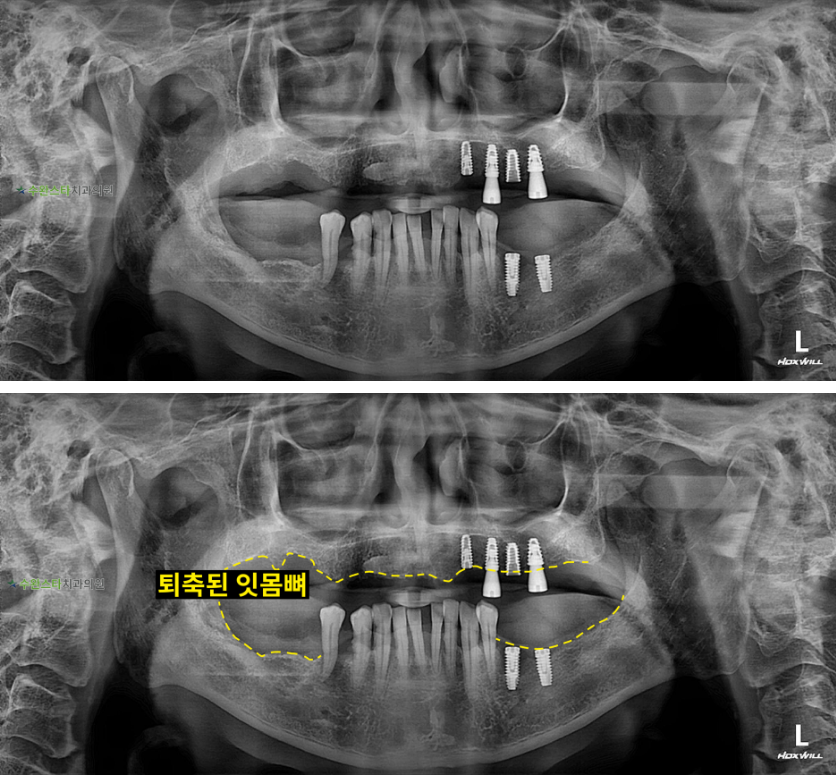

내원 시 파노라마

처음 내원 시 파노라마, 60대 남성 (2025. 12 촬영)

내원 시 파노라마 사진입니다.

자연치아가 있는 부분 이외의

잇몸뼈가 많이 녹아내린

상태입니다.

이전에 심은

임플란트를 제거 후

뼈 이식과  임플란트 식립을

진행하기로 했습니다.